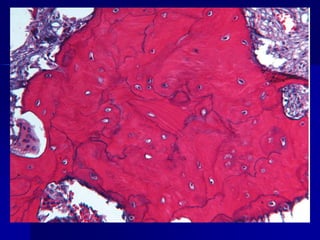

ENFERMEDADES CAUSADAS POR ALTERACIONES FUNCIONALES DE LOS OSTEOCLASTOSENFERMEDAD DE PAGET (OSTEITIS DEFORMANTE)    Desorden localizado de la remodelación ósea, causando una excesiva reabsorción del hueso correspondiente por un desorganizado reemplazo   del hueso, produciendo engrosamiento pero debilidad osea que es susceptible de deformarse y   fracturarse.  Comienza en los 40 años. Posible infeccion con virus lentos por paramixovirus.   Tres estadios:Osteolitica,Mezcla de osteoblastica-osteolitica. Osteoesclerotica.     Ordenamiento al azar de las lineas de cemento, creando un patron de mosaico de h. lamelares.Elevacionserica de F.alcalina

ENFERMEDADES CAUSADAS PORALTERACIONES FUNCIONALES DE LOS OSTEOCLASTOSENFERMEDAD DE PAGET (OSTEITIS DEFORMANTE) Desorden localizado de la remodelación ósea, causando una excesiva reabsorción del hueso correspondiente por un desorganizado reemplazo del hueso, produciendo engrosamiento pero debilidad osea que es susceptible de deformarse y fracturarse. Comienza en los 40 años. Posible infeccion con virus lentos por paramixovirus. Tres estadios:Osteolitica,Mezcla de osteoblastica-osteolitica. Osteoesclerotica. Ordenamiento al azar de las lineas de cemento, creando un patron de mosaico de h. lamelares.Elevacionserica de F.alcalina